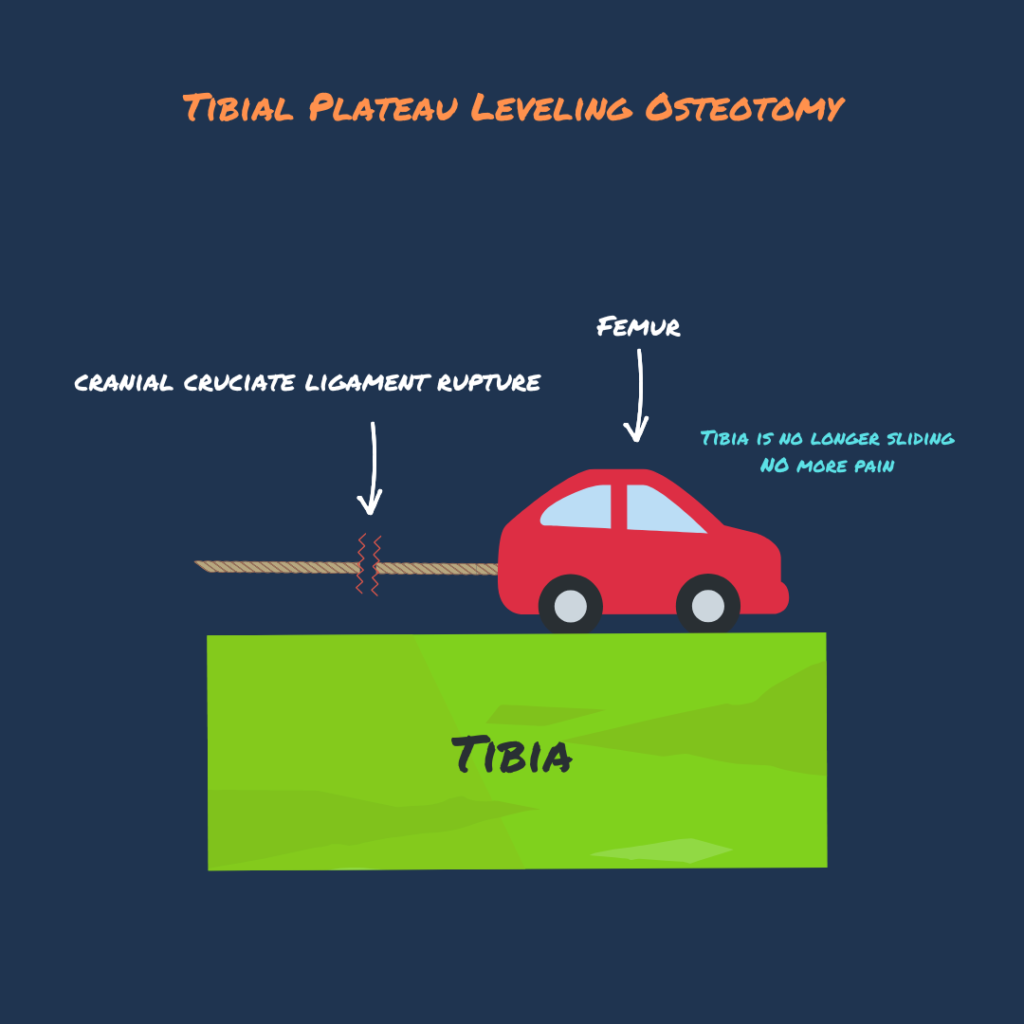

The Tibial Plateau Leveling Osteotomy (TPLO) procedure alters the angular relationship between the femur and tibia. The primary goal of this surgery is to reduce forward sliding of the tibia during movement. This is achieved by making a semicircular osteotomy at the proximal aspect of the tibia, rotating the proximal tibial segment, and stabilizing it with a bone plate to facilitate healing. This realignment of the articular surfaces within the stifle joint serves to enhance joint stability throughout the stride cycle and mitigate the development of future joint inflammation and osteoarthritis.